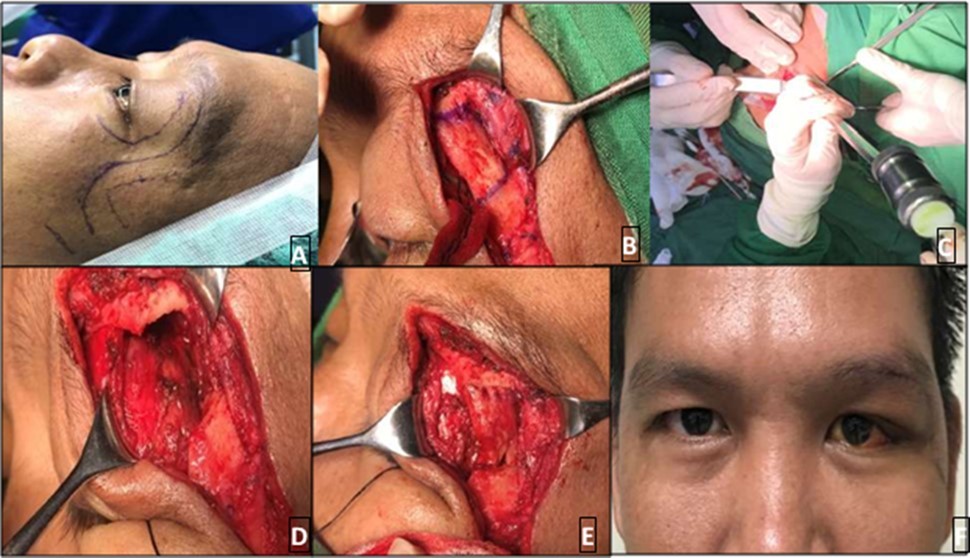

The patient was surgically managed with lateral orbitotomy and removal of the orbital mass under general anesthesia last July 23, 2019 (Figure 3). Skin marking was drawn over the following orbital landmarks: superior, inferior, lateral orbital rim and zygoma. A Stallard-Wright S-shaped lateral orbitotomy incision was made and dissection was carried down to the orbital rim periosteum. After incision of the periosteum, the lateral orbital rim was exposed and markings were placed for the periosteal flaps. Osteotomy was done using a bone chisel and mallet). After bone removal, part of the mass was visible, firm and fixed to surrounding structures. After careful dissection and release, the lesion was excised. No gross bone deformities were noted. The lateral orbital rim was repositioned . The periosteum was then closed over the bone to secure its position. The drain was placed, followed by subcutaneous closure then skin closure.

Figure 3.Skin marking of landmarks and incision B. Lateral orbital rim exposed and markings placed C. Osteotomy D. After bone removal, part of the mass is seen E. Lateral orbital rim was repositioned F. Day 11 post-op, grossly there’s marked improvement of previous globe displacement

He was referred to Oncology Service for further evaluation and planned radiotherapy to address possible tumor residual and prevent local recurrence. While surgical removal has improved globe position and reduced proptosis of patient’s left eye (Figure 3), treatment was not completed. Prognosis and the need for close follow-up were discussed extensively with the patient; however, he moved to another area and was lost to follow up.